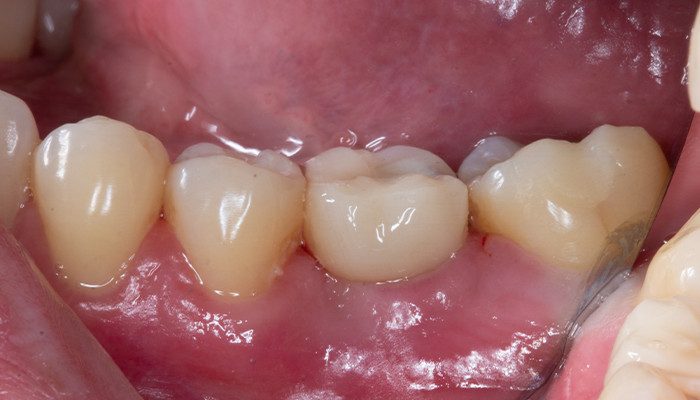

21 | Remoção de sutura e controle 10 dias de pós-operatório – 36 vista vestibular

22 | Remoção de sutura e controle 10 dias de pós operatório – 46 e 47 vista vestibular.